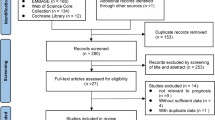

The aim of this study was to apply density correction method to the quantitative image analysis of non-small cell lung cancer (NSCLC) computed tomography (CT) images, determining its influence on overall survival (OS) prediction of surgically treated patients. Clinicopathological (CP) data and preoperative CT scans, pre- and post-contrast medium (CM) administration, of 57 surgically treated NSCLC patients, were retrospectively collected. After CT volumetric density measurement of primary gross tumour volume (GTV), aorta and tracheal air, density correction was conducted on GTV (reference values: aortic blood and tracheal air). For each resulting data set (combining CM administration and normalization), first-order statistical and textural features were extracted. CP and imaging data were correlated with patients 1-, 3- and 5-year OS, alone and combined (uni-/multivariate logistic regression and Akaike information criterion). Predictive performance was evaluated using the ROC curves and AUC values and compared among non-normalized/normalized data sets (DeLong test). The best predictive values were obtained when combining CP and imaging parameters (AUC values: 1 year 0.72; 3 years 0.82; 5 years 0.78). After normalization resulted an improvement in predicting 1-year OS for some of the grey level size zonebased features (large zone low grey level emphasis) and for the combined CP-imaging model, a worse performance for grey level co-occurrence matrix (cluster prominence and shade) and first-order statistical (range) parameters for 1- and 5-year OS, respectively. The negative performance of cluster prominence in predicting 1-year OS was the only statistically significant result (p value 0.05). Density corrections of volumetric CT data showed an opposite influence on the performance of imaging quantitative features in predicting OS of surgically treated NSCLC patients, even if no statistically significant for almost all predictors.